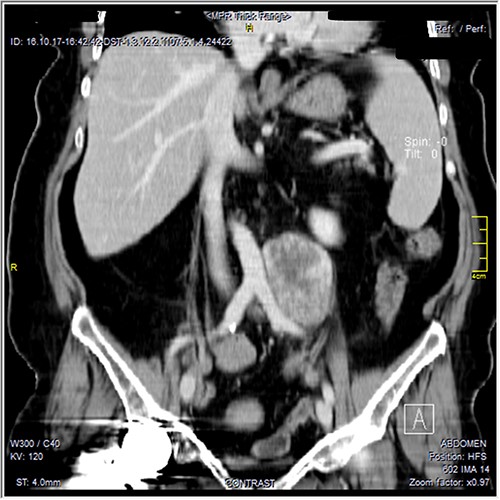

The CT scan was confirming the presence of a relatively well-defined retroperitoneal lobulated mass lesion seen extending along the left lateral wall of the distal abdominal aorta and left common iliac artery and anteromedial to the left psoas muscle. It showed heterogeneous intense peripheral enhancement during the porto-venous phase, the fat planes were preserved between the lesion and adjacent structures with no gross evidence of local invasion (Figs 1–3). The first diagnostic possibility was made as a retroperitoneal paraganglioma based on the CT appearance. The surgical decision of tumor removal was done.

Contrast-enhanced axial CT images—soft tissue window, show well-defined peripherally enhancing mass lesion at left para-aortic region. No local invasion.